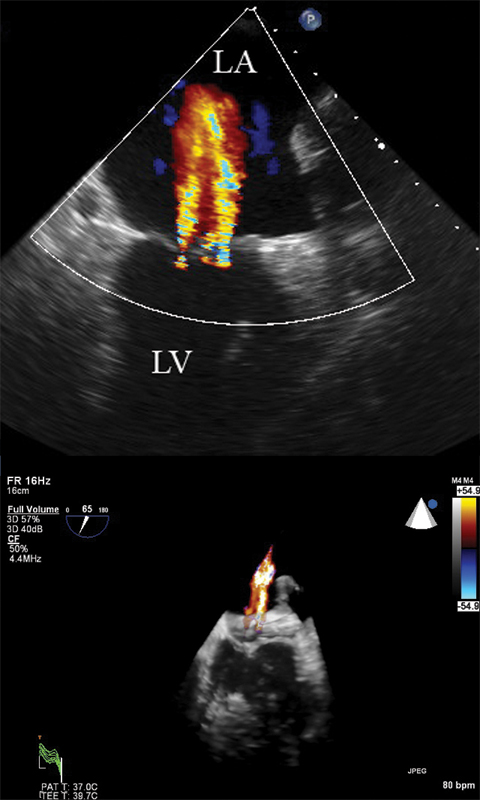

فحوصات تشخيصية لبعض امراض القلب والشرايين التاجية